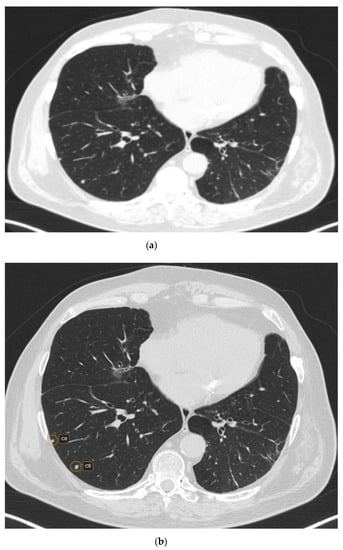

Out of 481 possible nodules detected by CAD, 12 were rejected by the radiologist, being considered false positive. The main reasons for false positives included fibrosis—five (41.66%) nodules; broncho-vascular structures—six (50%) nodules; and artifacts due to respiratory motions—one (8.33%) nodule. The majority of the false positive nodules were located in the parahilar area—seven (58.33%) nodules. Regarding the size of the false positive nodules, four (33.33%) had <6 mm, seven (58.33%) had between 6 and 8mm and one (8.33%) had > 8 mm (Figure 1 and Figure 2).

Figure 1. CT scan (lung window) showing raw CT images (a) versus marked CT images using CAD (b).